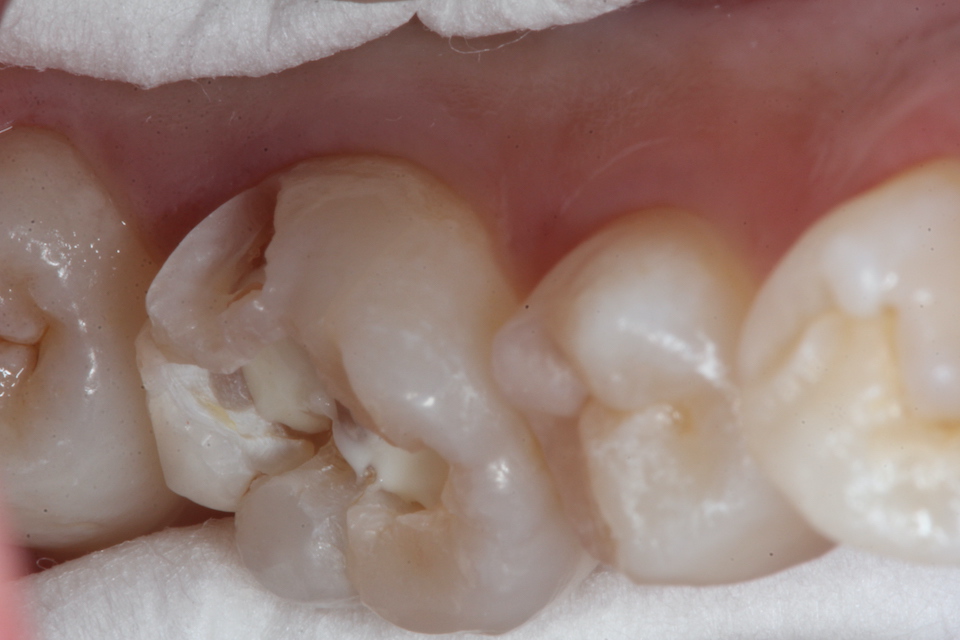

この子は2年後に象牙質の虫歯の進行によりエナメル質が欠けたので再治療した。内部の象牙質がほとんどなくなっているので、過大な咬合力に耐えられない。どうしたものか。。

・・突然歯が欠けたということでやってきた。内部の象牙質は虫歯になっていてプロセスチーズくらいの柔らかさになっていた。多数のクラックが見えると思う。

破折面を見てみると面白いことがわかる。内側から狐色の軟化象牙質(虫歯)、白い脱灰(腐食)が始まっているエナメル質、外側の半透明層が健全なエナメル質だ。なぜこうなるのか?現在の歯科医学の水準では説明が付かない。電気化学的になら説明ができるが、ちょっと眠たくなってきたので、日を改めて。